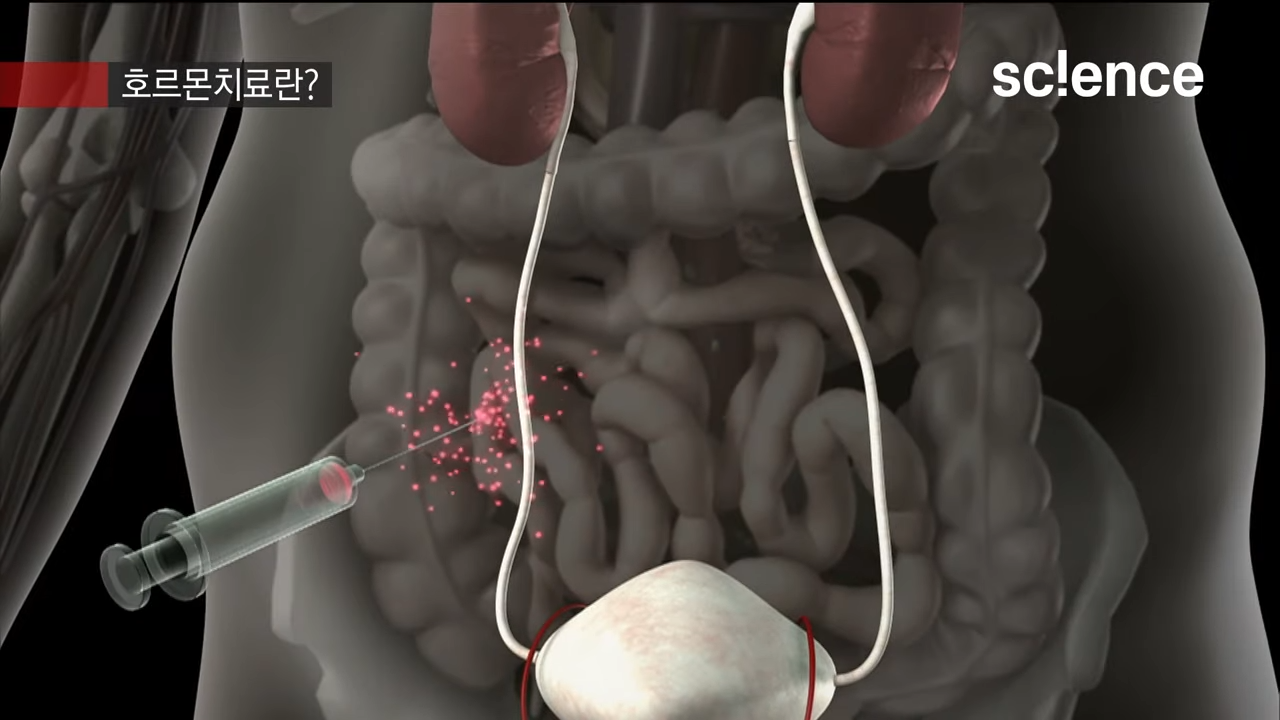

EBS 컬렉션 사이어스 - 유튜브 영상

명의가 알려주는 전립선암